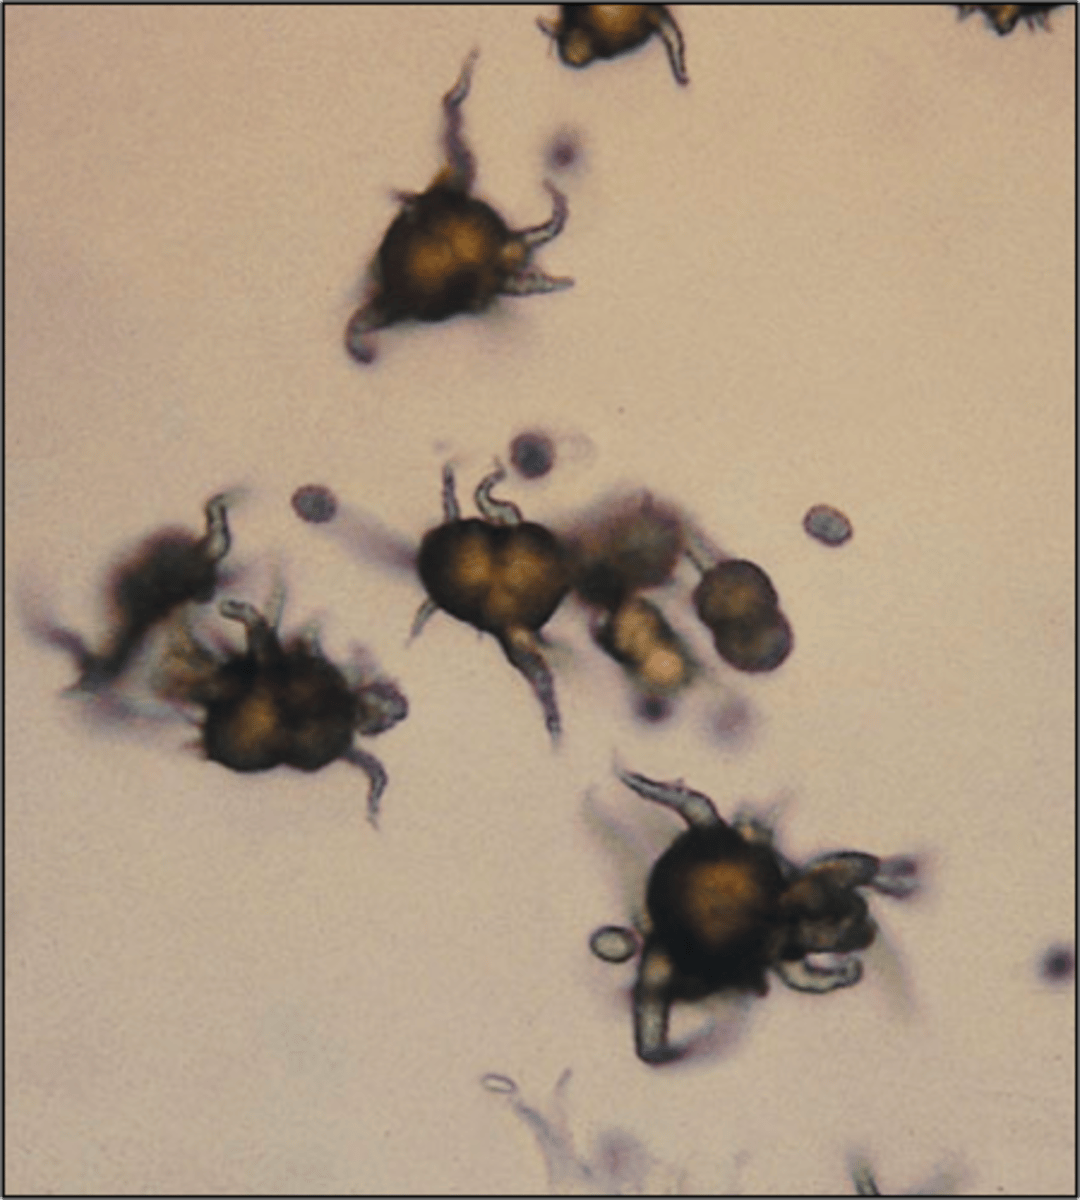

ammonium (bi)urate crystal

urine

round, golden brown in color with irregular spicules